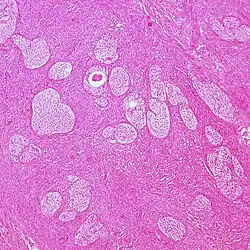

Mucinous tumor 15% 8.8% Benign mucinous tumors of the ovary consist of simple, nonstratified columnar epithelium with basally-located hyperchromatic nuclei and resemble gastric foveolar epithelium.[9]